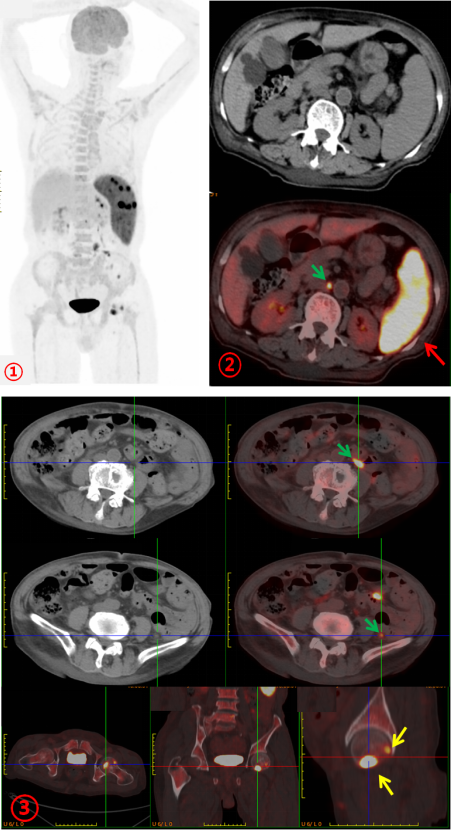

為進一步明確病情,完善PET/CT檢查。PET/CT示:脾臟彌漫性增大伴FDG代謝明顯不均勻增高(SUVmax約22.3;圖1、2,紅箭),腹膜后及腹腔內多發FDG代謝增高結節(SUVmax約8.8;圖1、2、3,綠箭),全身多發骨骼FDG代謝增高,左股骨頭為著,(SUVmax約11.7;圖1、3,黃箭),骨骼未見明顯破壞。PET/CT診斷為淋巴瘤。患者隨后完善骨髓活檢,病理診斷為:小B細胞淋巴瘤。